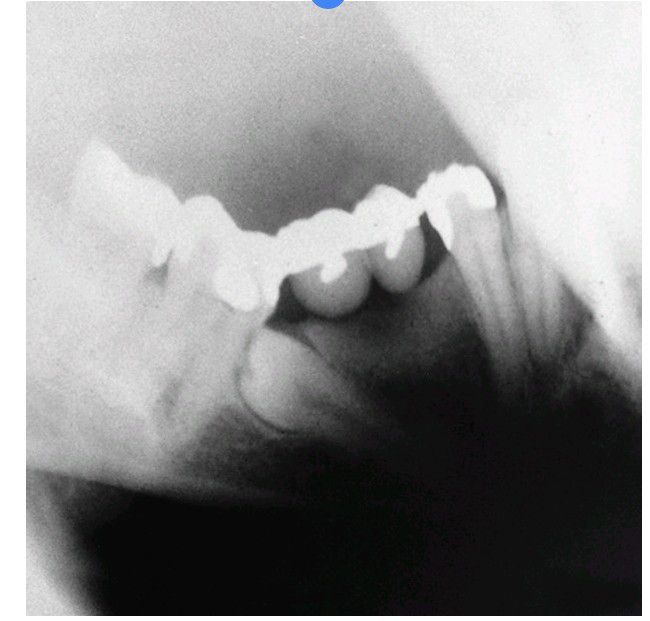

Impacted teeth under fixed prosthesis

Impacted tooth under a fixed bridge. The tooth must be removed and therefore may jeopardize the bridge.